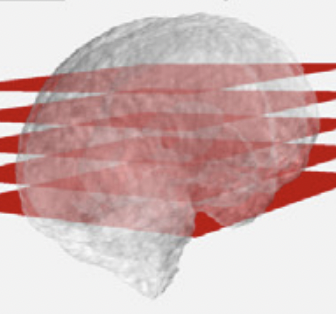

Sensorless volumetric reconstruction of fetal brain freehand ultrasound scans with deep implicit representation

Medical Image Analysis

·

01 May 2024

·

doi:10.1016/j.media.2024.103147